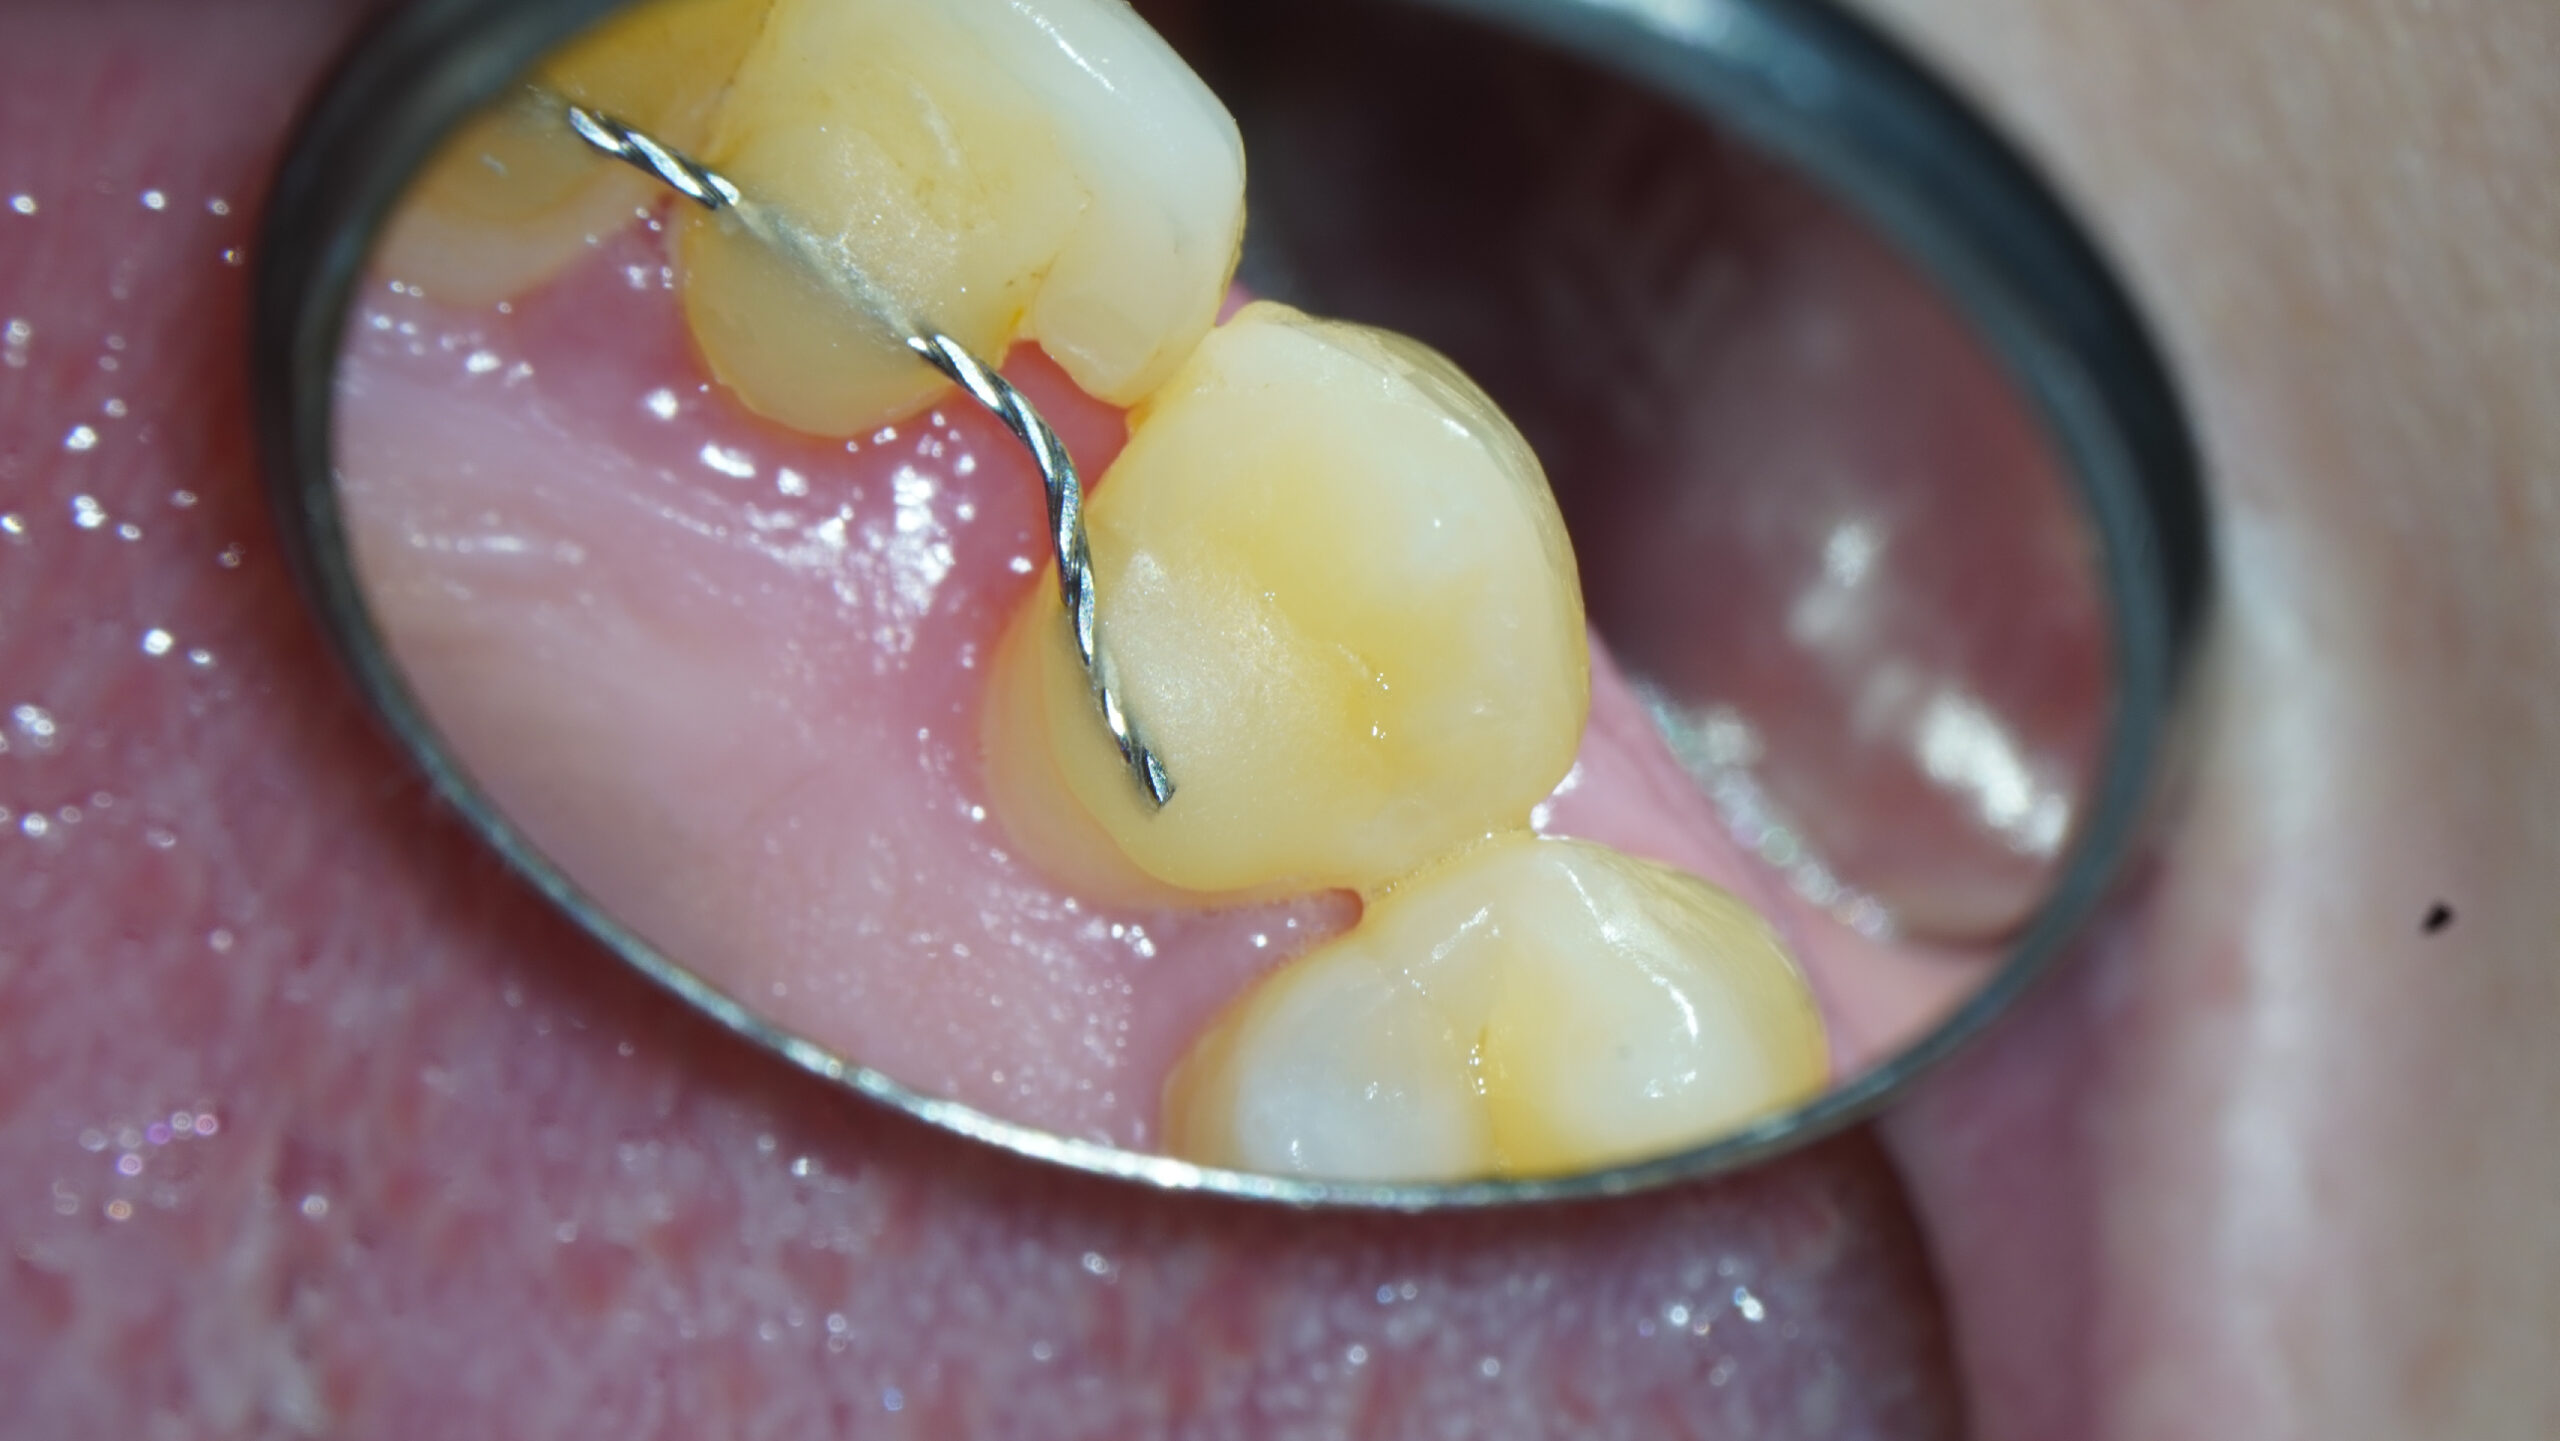

Imágenes del tratamiento

* Haz click sobre las imágenes para verlas a mayor tamaño y a color